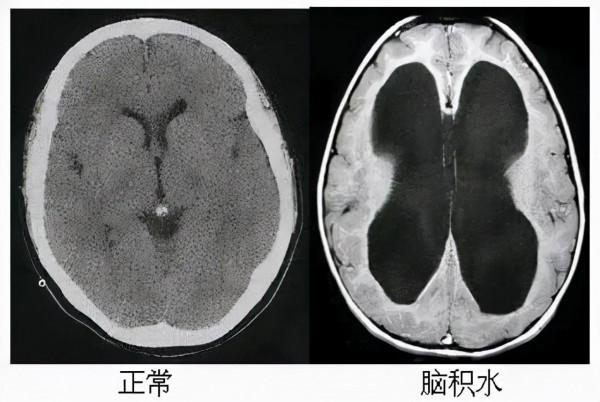

大腦中的“水庫”發生缺水有危險,但要是腦室中產生的腦脊液過多,也就是水多了,就是腦積水,腦積水的定義是:顱內蛛網膜下腔或腦室內的腦脊液異常積聚,使其一部分或全部異常擴大,情況也會十分危急,多數腦積水是需要治療的。

首先會導致兩個側腦室不斷擴大,從而壓迫周圍的腦組織,使它逐漸變薄,引發神經性損傷。